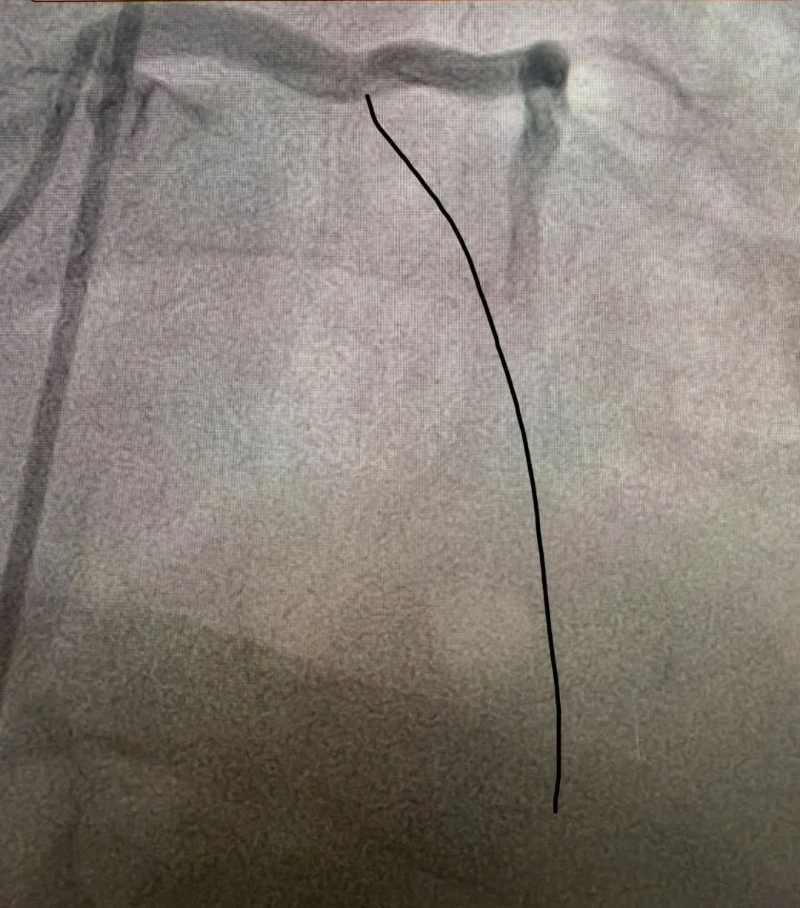

心臟恢復跳動意味著有了手術(shù)機會,患者被迅速送入介入室。介入室技師和護士早已準備就緒,惠州市中心人民醫(yī)院博羅分院麻醉科醫(yī)生也已到位。手術(shù)由溫靈武和文軼醫(yī)生共同完成。造影顯示,患者前降支開口處完全閉塞,醫(yī)生迅速開通閉塞血管并植入支架一枚,術(shù)后血流恢復良好。從患者進入介入室到血管開通,僅用時20余分鐘。

造影見前降支

開口就完全閉塞

手術(shù)后血流恢復